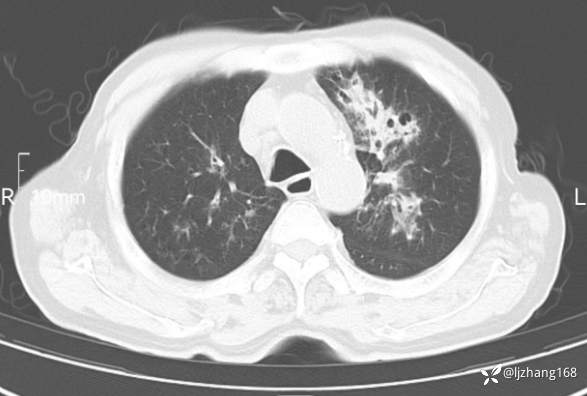

老年男患,咳嗽,气短,双肺多发间质性病变,何种感染?(有结果)

辅助检查:胸部CT:双肺肺气肿,间质性病变,血气分析:PH 7.413, PCO2 29.2mmHg, PO2,81.8mmHg,乳酸 3.3mmol/1,剩余碱-4.0mmol/1,HC03 18.8mmol/1。全血超敏C反应蛋白:超敏C反应蛋白 135.60 mg/L、 白细胞 14x19^9/L,中性粒细胞11.6x10^9/L。